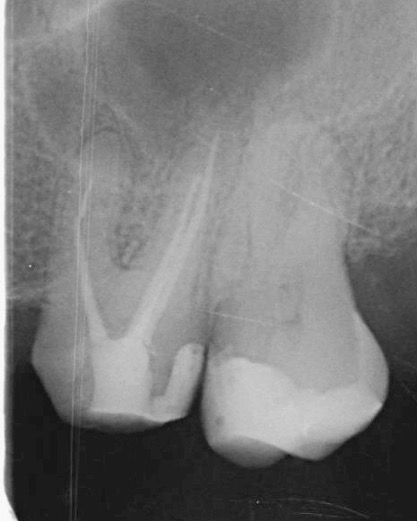

Tedavi esnasında dişin meziobukkal kanalının apikal üçlüsünde alet kırığı meydana geldi. İlgili kırık alet bypass yapılmaya çalışıldı ancak başarılı olunamadı ve kanalda basamak oluştu. Dişin vital olduğu da göz önünde bulundurularak kök kanalları doldurularak dişin takibine karar verildi (Şekil 2).

(Şekil 2) 2023 Mayıs Post-Op radyografi